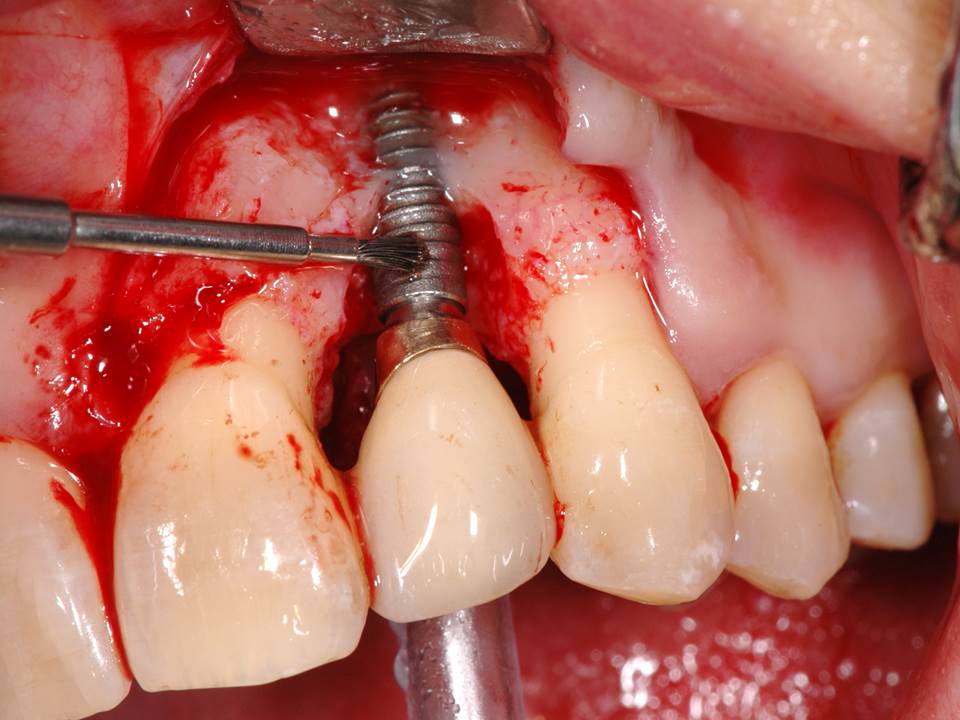

Periimplantitis – entzündete Zahnimplantate können gerettet werden !

Zahnimplantate sind statistisch gesehen die sicherste Zahnersatzversorgung. Wenn beim Einsetzen der Zahnimplantate alles richtig gemacht wurde, also vom Zahnarzt um das Zahnimplantat ein Ring aus festen Knochen und festem Zahnfleisch aufgebaut wurde, dann steht einer dauerhaften Implantatgesundheit mit Erfolgsraten von über 95% nichts im Wege. Trotzdem sind Zahnimplantate wie die eigenen Zähne auch von Entzündungen und Verlusten bedroht. Besonders kritisch wird es, wenn sich Zahnfleischtaschen gebildet haben, in denen Bakterien leben, die nicht mehr von der normalen Mundhygiene erreicht werden können. Ein Anzeichen für die Periimplantitis ist Zahnfleischbluten, schlechter Geschmack und Zahnfleischschwellung. Die Infektion in der Tasche kann sich schnell ausbreiten und zu einem Verlust von Knochen um das Implantat führen, bis es locker wird und ausfällt.